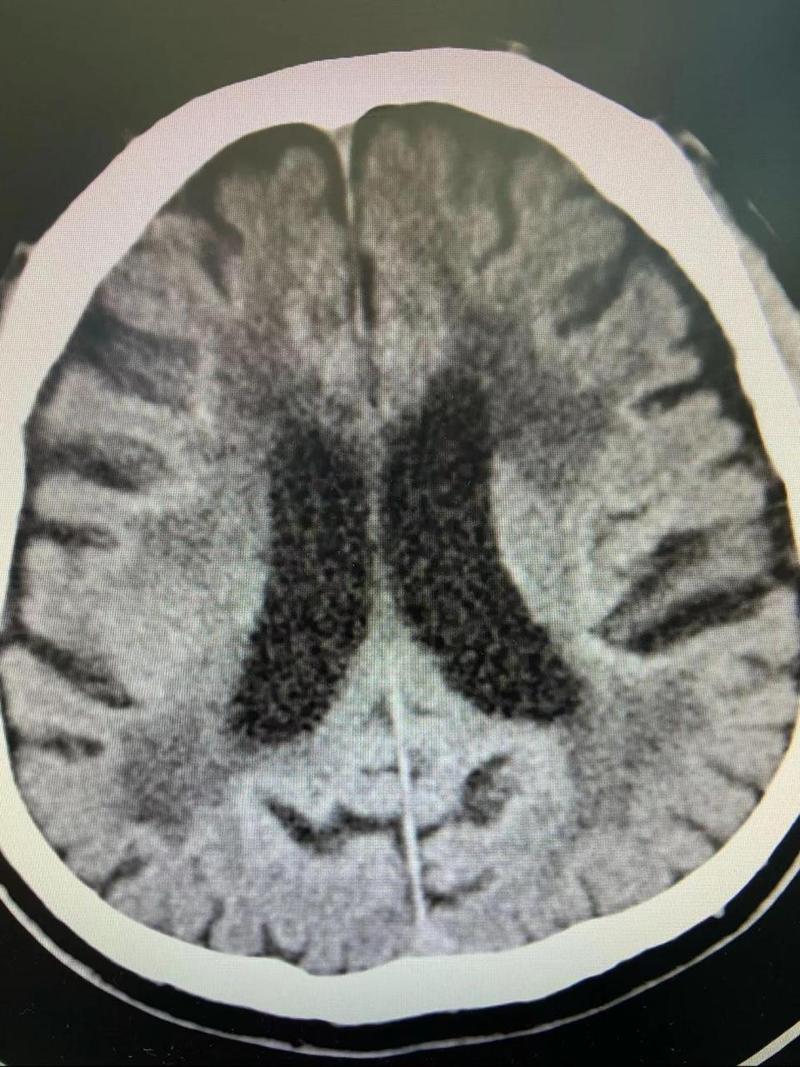

(图片来源网络,侵删)